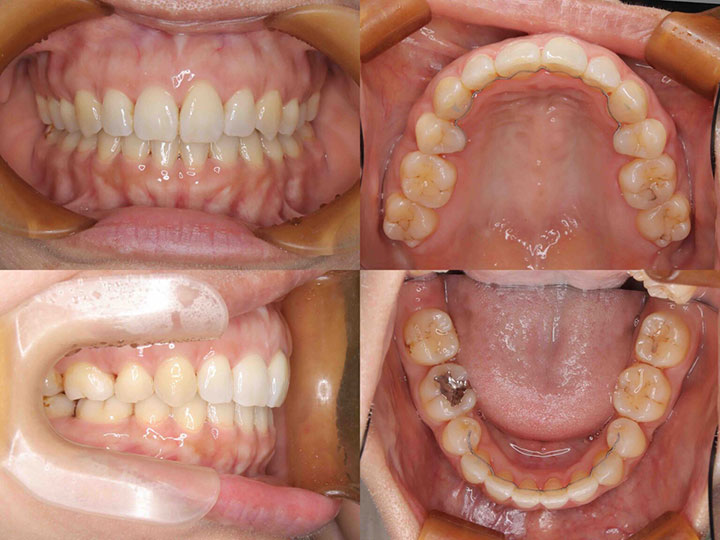

口の閉じ辛さの治療

治療期間:1年5ヶ月

上下顎4番を抜歯して、前歯を後方に移動しました。